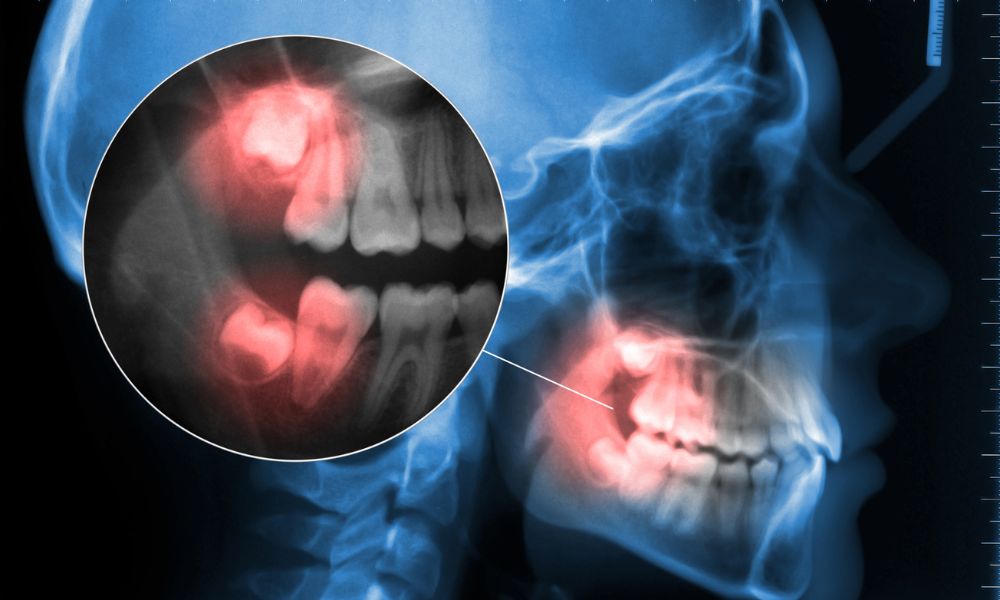

Proceso de erupción de las muelas del juicio

La salida de estas muelas puede causar dolor e inflamación. Algunas crecen en ángulos incorrectos o se quedan dentro del maxilar. Esto puede provocar infecciones, caries o quistes en la mandíbula.

La erupción de las muelas del juicio puede causar problemas cuando no hay espacio suficiente. La American Dental Association sugiere considerar la cirugía si hay dolor en estas piezas. Veamos algunos problemas frecuentes relacionados con las muelas del juicio.

Falta de espacio en la cavidad bucal

Las muelas del juicio pueden quedarse atrapadas en la mandíbula sin espacio suficiente. Esto puede provocar infecciones o quistes que dañan otros dientes y el hueso. La cirugía puede ser necesaria para prevenir daños y mantener una buena salud bucal.

Infecciones y pericoronaritis

Las muelas del juicio que emergen parcialmente pueden causar infecciones en las encías. La pericoronaritis es una infección común que inflama el tejido alrededor del diente retenido.

Si no se trata, la infección puede extenderse y causar complicaciones graves. Es importante atender estos problemas a tiempo.